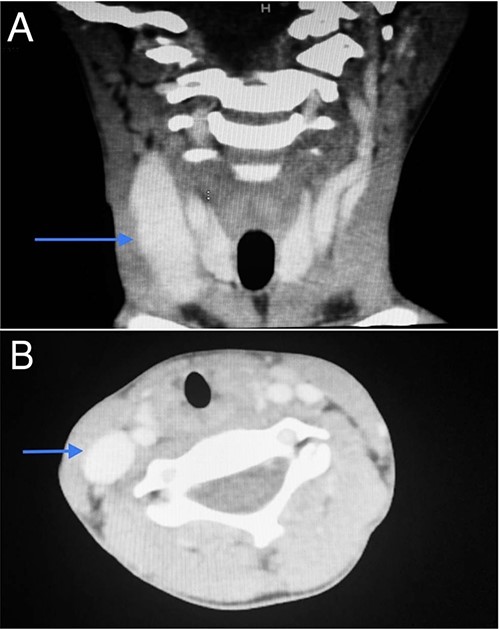

Imaging examination of the patient was done by performing CT with contrast and US. US Doppler showed a right dilated internal jugular vein during coughing and the valsalva maneuver (Fig. 5). CT showed a wide right internal jugular vein (Fig. 6). Both cases managed conservatively with follow-up and no surgical intervention as they did not have any complication or cosmetic concerns.

CT scan of the second patient in coronal view (A) and axial view (B) with blue indicate internal jugular phlebectasia.